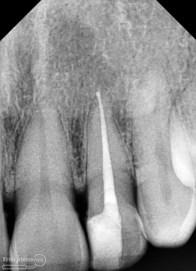

Setelah itu dilakukan pengambilan ronsen kembali…

Alhamdulillah perawatan ini tidak ada kendala dan bisa diselesaikan dalam satu kali kunjungan langsung dua gigi… Ronsen sangat penting dalam prosedur perawatan saluran akar, jadi pesan saya adalah “No Xray, No Endo” 🙂